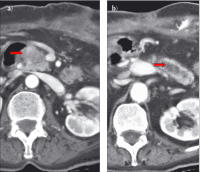

Abbildung 5: Die sich erstmals darstellende hypodense Raumforderung (→) im Pankreaskopf führt zu b) zunehmender Pankreasgangerweiterung (→) im Korpus/Schwanz (CT 13.9.05).

Keywords: chronische PankreatitisComputertomographieCTGastroenterologie